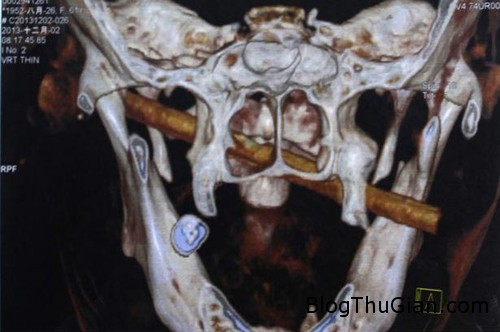

Thanh tre dài 12 cm mắc kẹt trong mặt của bà Fu JinFeng. Ảnh: Mirror

Cụ Fu Jinfeng, 61 tuổi, bị một thanh tre đâm xuyên qua mặt nhưng không hề hay biết cho đến khi gia đình đưa cụ đưa tới bệnh viện kiểm tra tình trạng sức khỏe, Mirror cho hay.

Sau khi phát hiện cụ không thể há miệng để ăn và vết thương ở miệng không thể lành lại, gia đình đưa cụ tới bệnh viện Xiang Ya thuộc tỉnh Hồ Nam. Các bác sĩ ở đây rất sửng sốt khi kết quả chụp chiếu cho thấy một vật thể lạ tương đối lớn cắm xuyên qua mặt cụ.